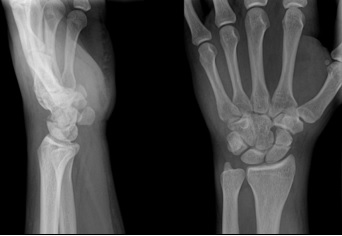

Seorang laki-laki, 43 tahun, datang ke IGD RS dengan keluhan nyeri pada tangan kiri akibat jatuh dengan tangan terjulur dari sepeda motor yang dikendarainya 2 jam sebelum masuk RS. Pemeriksaan fisik: nyeri tekan pada tabatiere anatomique.

Apa diagnosis paling tepat?

| Fraktur capitatum sinistra | |

| Fraktur lunatum sinistra | |

| Fraktur scaphoid sinistra | |

| Fraktur trapezium sinistra | |

| Fraktur trapezoidum sinistra |